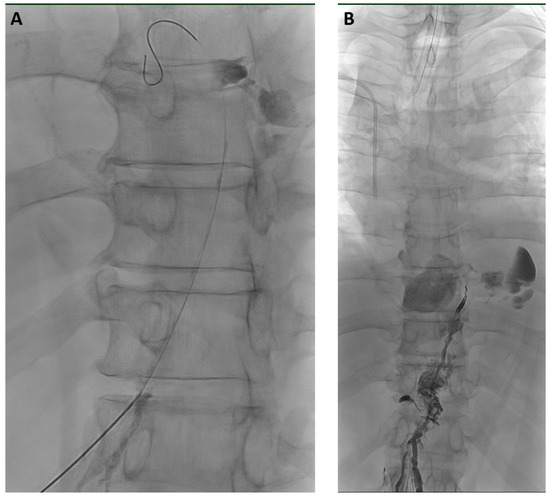

2.2. Interventional Technique

3.4. Clinical Success